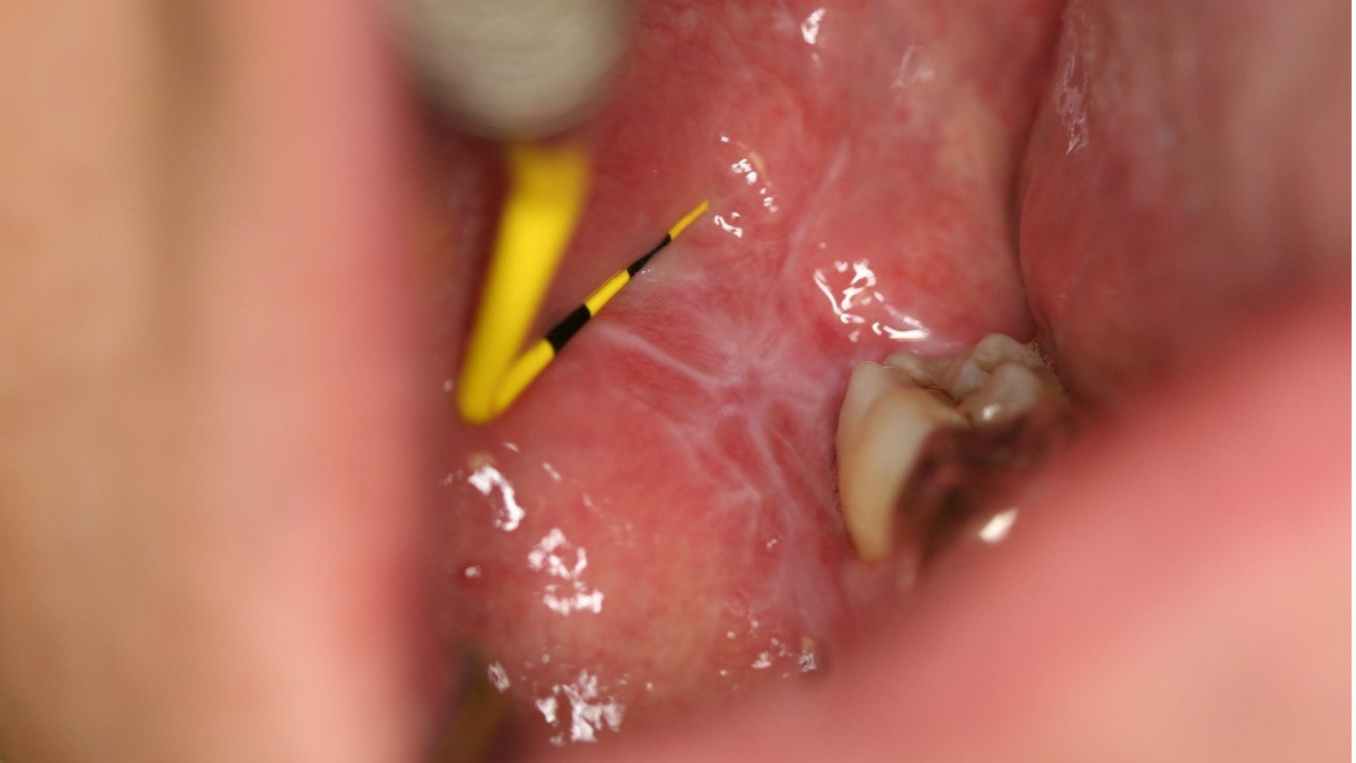

Lichen Planus

This review of oral white lesions and their identifying factors can be a guide for dental hygienists to determine whether referral to a specialist is necessary.